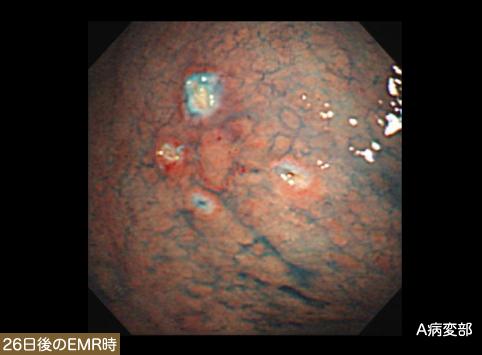

疾患(病理主体)の分類悪性上皮性腫瘍/印環細胞癌

部位(臓器別)胃(部位)/体部

腫瘍の肉眼分類0型(表在型)/IIa型(IIa+IIb)

病変の最大径(ミリ)35〜40

腫瘍の深達度m